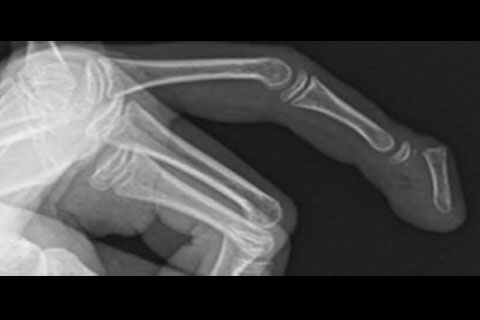

A Seymour (see-more) fracture is a break in the bone at the end of the finger or toe at the first

joint (Picture 1). It often happens when a finger

or toe is crushed or bent back too far.

A doctor or health care provider will ask what happened, examine your child, and take X-rays of the finger or toe.